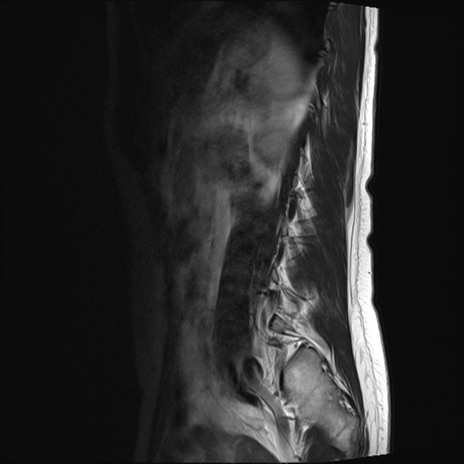

【整形】TIPS症例4 腰椎MRI T2WI(矢状断像)

腰椎MRI

STIR(矢状断像)